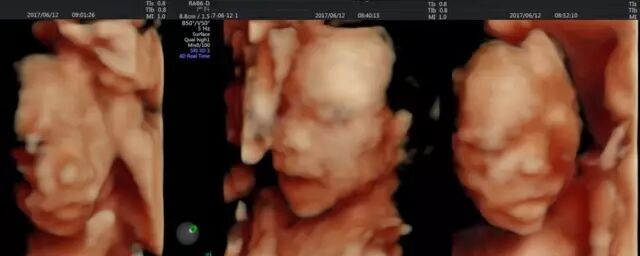

三个婴儿互相依偎,其中一个斜靠在另一个身上,剩余一个默默在旁小嘴时不时的吞咽着。位于上面小伙伴时不时的动一下,一张温馨到无法言说的画面油然生成,但这个温馨的场面不是发生在哪张温馨的床上,而是发生在临平妇产医院超声科一位三胞胎妈妈的子宫里!

今天是丰女士和丈夫预约做四维彩超的日子,22周+5天丰女士的肚子已是比普通的孕妈大很多了,要见到宝宝的模样,丰女士和丈夫都有点小紧张更多的是期待。

“这是其中一个宝宝的小脸,似乎是睡着了….”影像科郑书明主任一边转动着探头一边说着。

丰女士和丈夫一直看着液晶屏,眼睛都不舍得眨一下,似乎都不想错过孩子们的一举一动。脸上的笑容洋溢着幸福,瞬间幸福感爆棚。